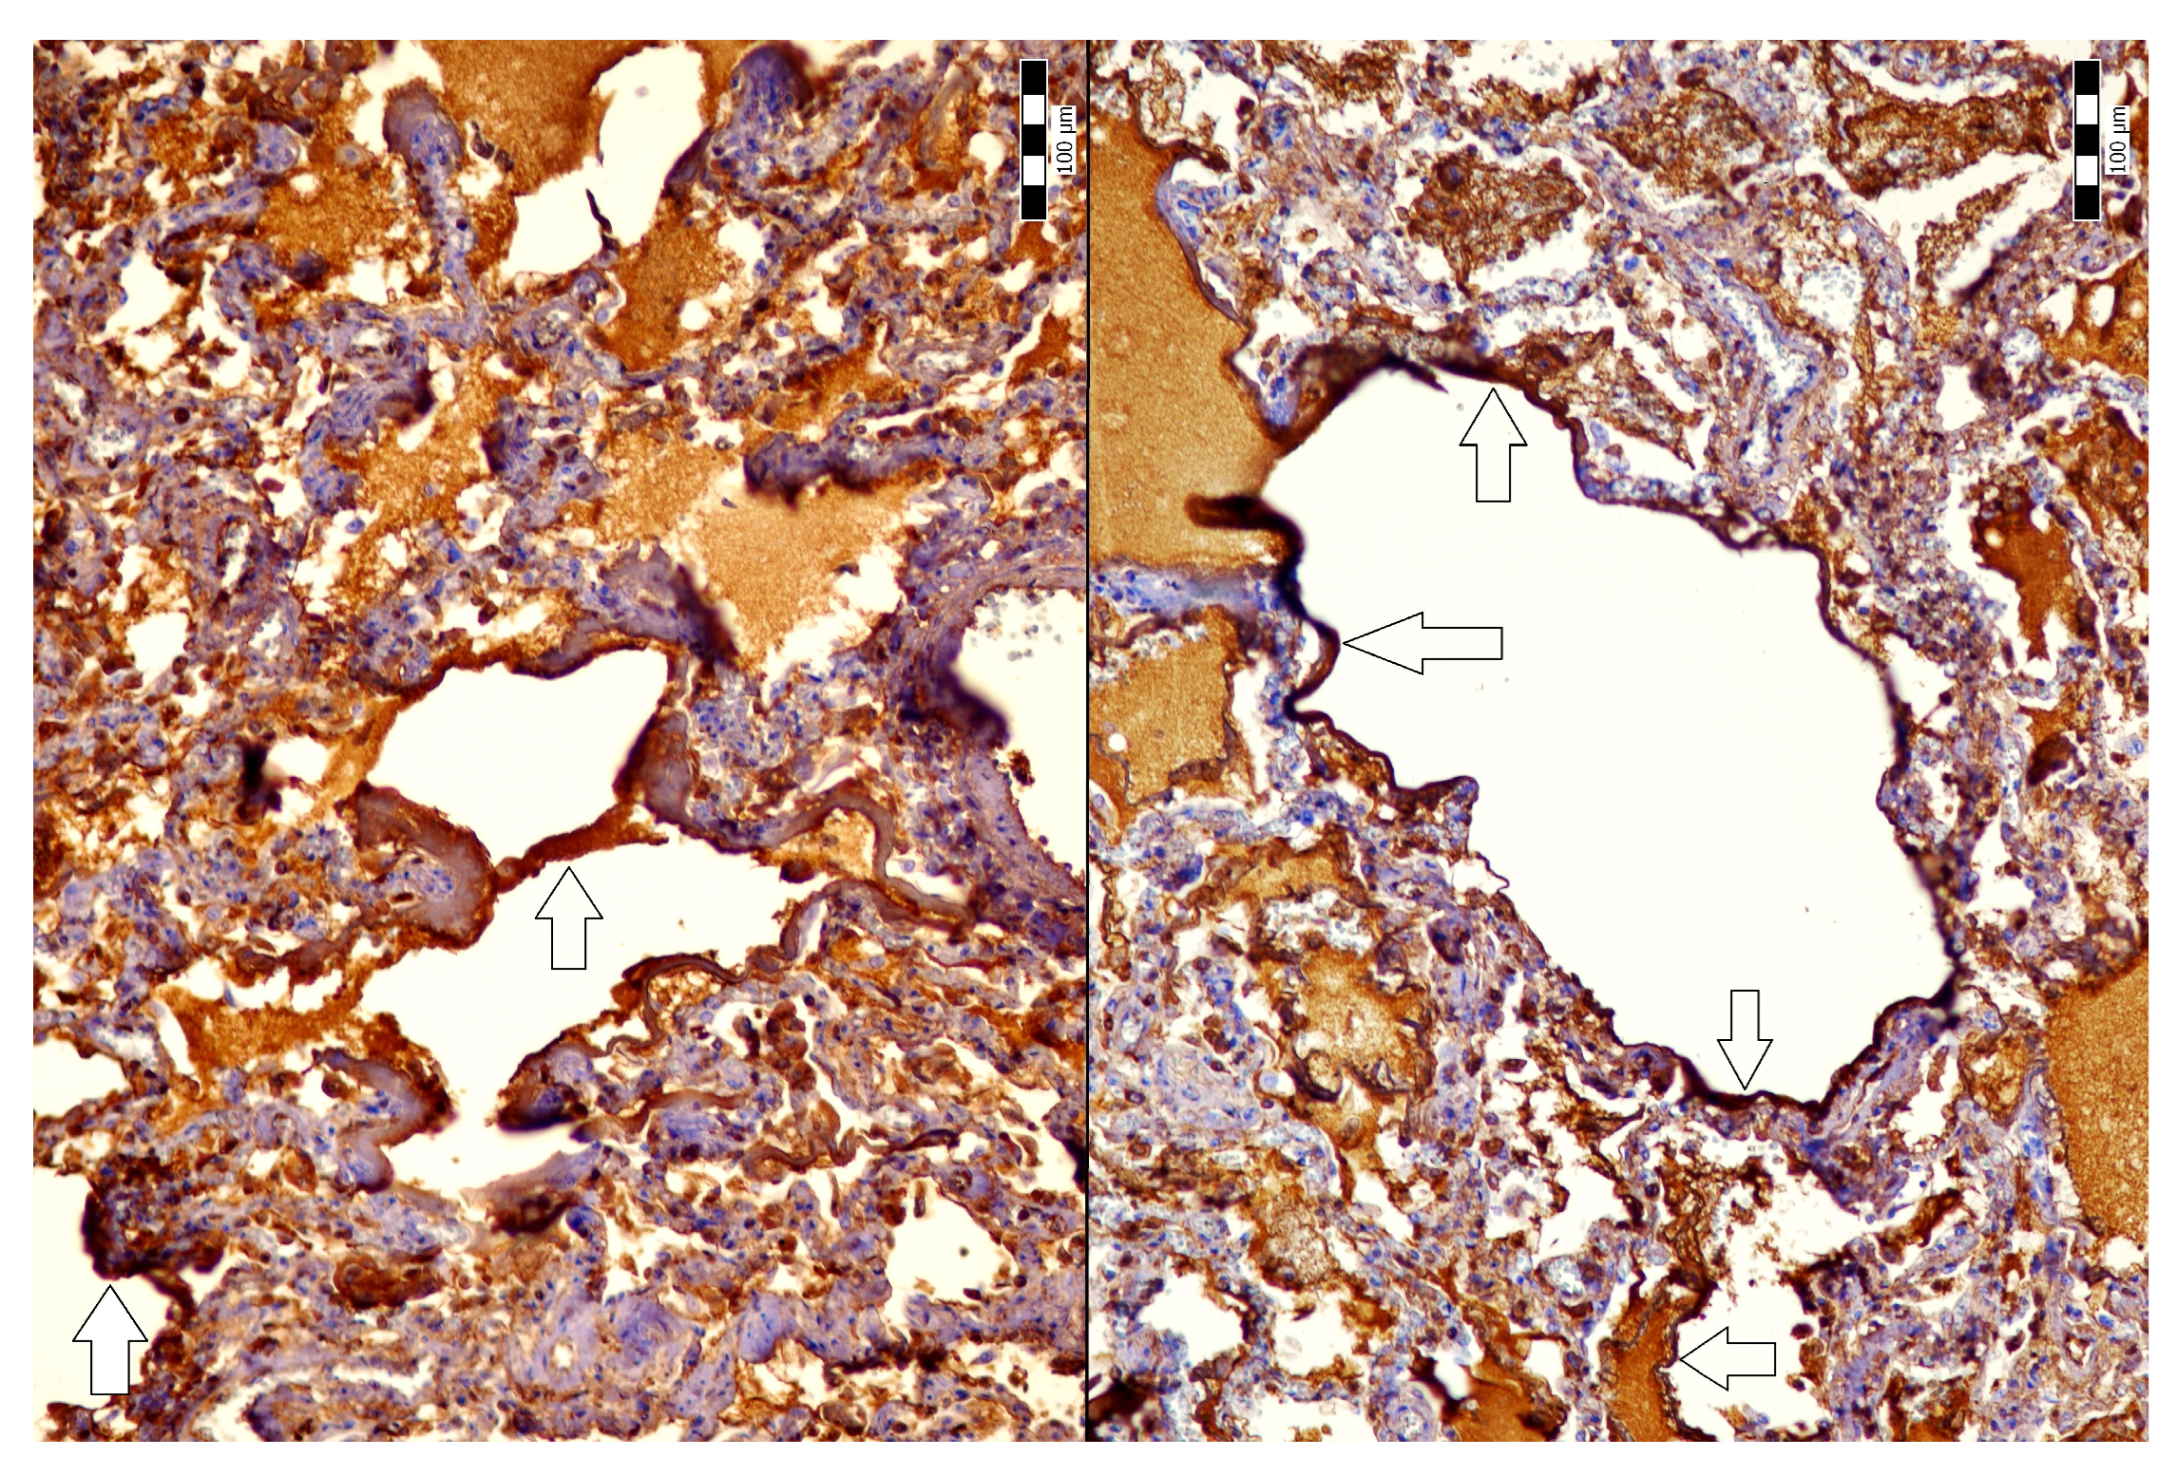

2. Case Description